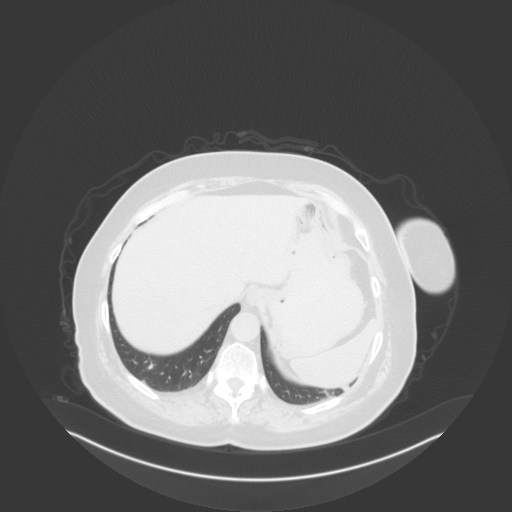

Original NATIVE CT scan (input)

Full window (WL 1023.5, WW 4095 β†’ Low βˆ’1024, High +3071)

Generated VENOUS CT scan (A→B translation)